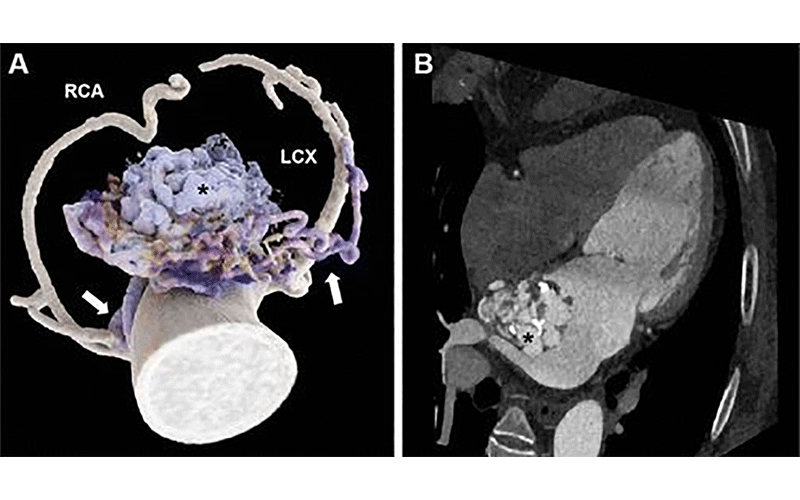

The first runner-up for this year’s Top Images in Radiology is entitled “Cinematic Rendering of Complex Coronary Artery Left Atrial Fistula” by Mingxi Liu and Xiaojuan Guo (2). The axial images showing multiple sinuses draining into the left atrium from the coronary arteries, although striking, may not allow for easy tracing of the vasculature. The crisp images postprocessed with cinematic rendering (Fig 2), however, carefully depict this unusual entity of complex coronary artery left atrial fistula and help the interpreting radiologists reach the final diagnosis.